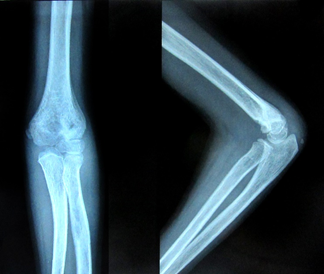

All the fractures united with no loss of carrying angle or cubitus varus deformity. According to Flynn’s grading system for elbow function, 41 patients (89.1%) achieved excellent results and one patient had poor result as shown in Table 2. Five patients (10.8%) had superficial pin site infection that went to heal with local pin site dressings only. None of them had chronic discharge after the wire removal. No complications like ulnar nerve injury, vascular injury, compartment syndrome, myositis ossificans, malunion, and non-unions were noted (Figures 1-4).

Figure 3 Follow-up X-rays (4th week) after pin removal.